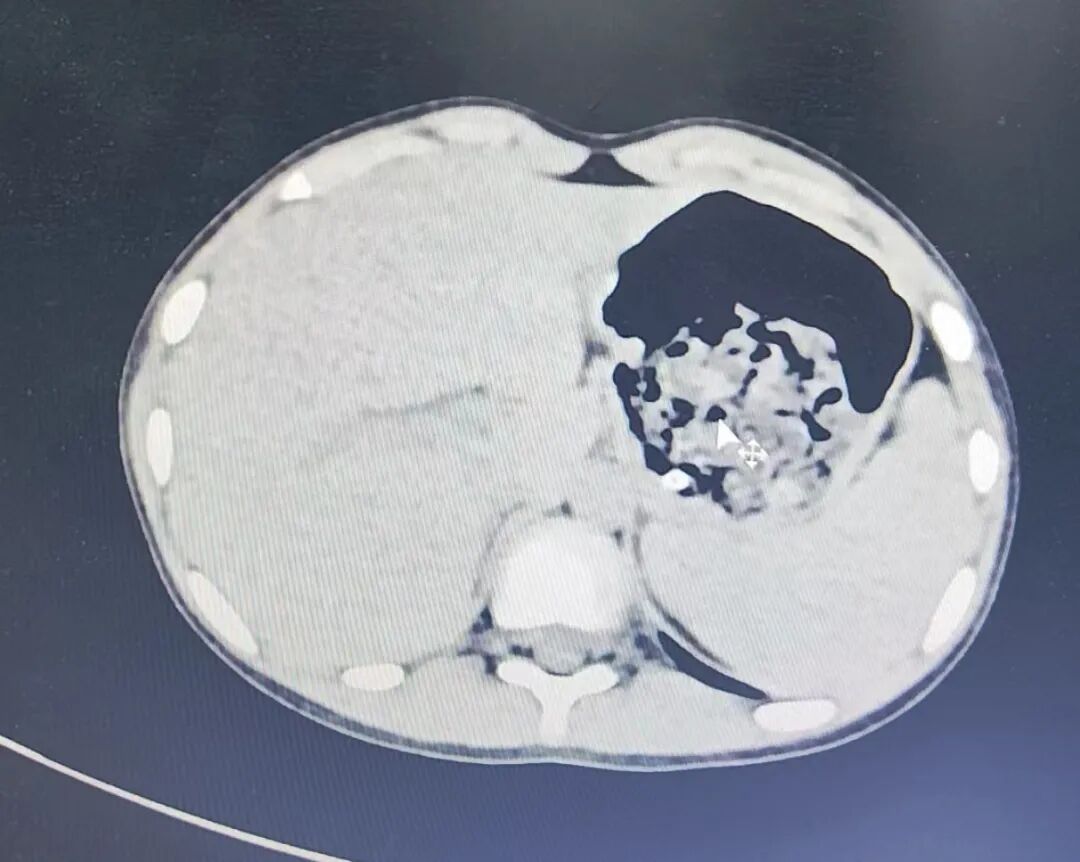

检查结果却让医生和父母都很吃惊:孩子胃里有一大团丝状异物,看样子像是头发,占据了2/3胃腔。

接诊的普外科主治医生秦鑫锞判断,欣欣腹痛呕吐的原因,很可能是因为吞食了大量头发,由于毛发组织不能消化,大量的毛发和食物残渣混合后,形成紧紧缠在一起的团块样物,俗称胃毛石症。

毛石堵在胃里影响食物消化、营养吸收,甚至还会导致患儿出现明显贫血和营养不良。